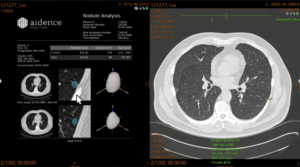

The industry-leading artificial intelligence from Aidence is supporting the TMC lung cancer screening service. Around three-quarters of lung cancer cases are diagnosed at a late stage in the UK and 10-year survival is poor (10%), but 79% is preventable (according to www.cancerresearchuk.org). The AI tool from Aidence, Veye Lung Nodules, helps identify any suspected lung nodules (even nodules as small as 3mm). This AI solution facilitates early lung cancer detection and can thus help save patients’ lives. Approximately 10,000 cases will be analysed by Aidence’s AI solution this year. It can be expected that about 10% of the patients will have a positive finding. (According to Gareth Davies, TMC UK Medical Director).

Aidence is marking a lung nodule in the images on the right (CT Thorax)

Aidence is marking a lung nodule in the images on the right (CT Thorax)